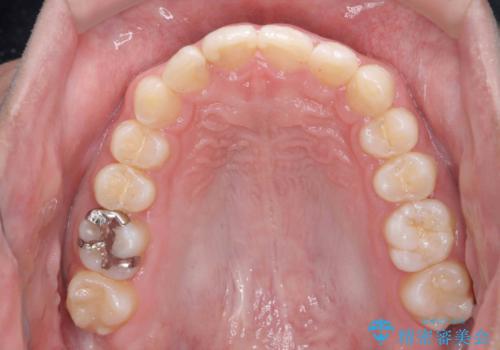

左のかみ合わせが1本分ずれていましたが、機能的には問題ないのでそのまま変えずに治療しています。

ずれている分を、上の歯を1本抜くか(ワイヤー矯正になります)、右上の奥歯を1本分後ろに送るか、そのまま前歯を並べるのかを選んでいただきました。

右のかみ合わせをそのままに、最小限の動かし方で見た目を改善しました。